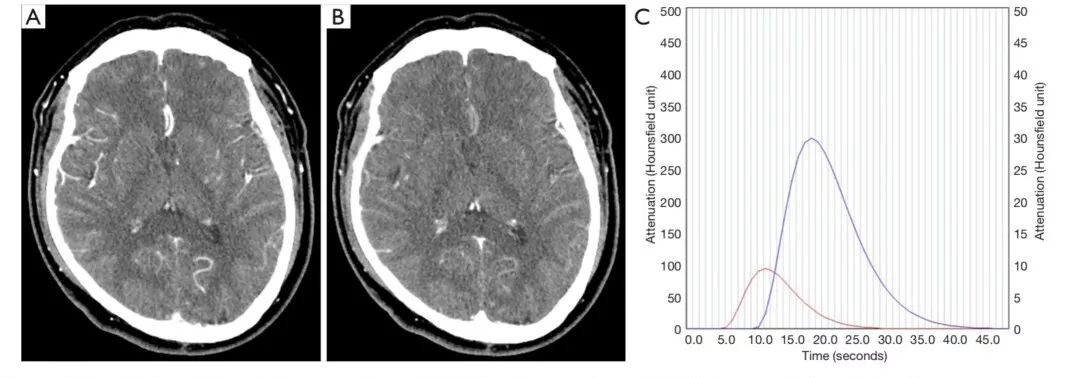

图1. CTP动脉期和静脉期的原始图像。A.CTP动脉期原始图像;B.CTP静脉期原始图像;C.CTP动脉期和CTP静脉期的时间--密度曲线(TAC);水平轴表示时间(秒),垂直轴代表密度。采集时间50秒,每秒对应一副图像。所示病例中,扫描开始后12秒时动脉期时间--密度曲线达到峰值,12秒定为动脉期。19秒时静脉期时间--密度曲线达峰值,19秒定为静脉期。